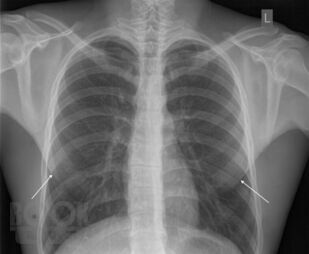

Рентгеноанатомия органов грудной клетки

В данном электронном пособии систематизированы и подробно изложены сведения о рентгеновской анатомии органов грудной клетки.